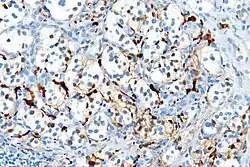

| Micrograph of a carotid body tumor (a type of paraganglioma) | |

On microscopic inspection, the tumor cells are readily recognized. Individual tumor cells are polygonal to oval and are arranged in distinctive cell balls, called Zellballen.[9] These cell balls are separated by fibrovascular stroma and surrounded by sustentacular cells.

With immunohistochemistry, the chief cells located in the cell balls are positive for chromogranin, synaptophysin, neuron specific enolase, serotonin, neurofilament and Neural cell adhesion molecule; they are S-100 protein negative. The sustentacular cells are S-100 positive and focally positive for glial fibrillary acidic protein. By histochemistry, the paraganglioma cells are argyrophilic, periodic acid Schiff negative, mucicarmine negative, and argentaffin negative.

Micrograph of a carotid body tumor -

S100 immunostain highlighting the sustentacular cells in a paraganglioma -